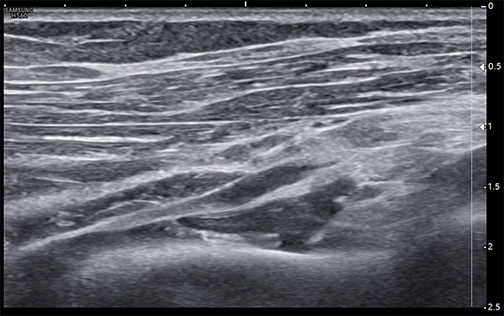

Unlabeled long-axis ultrasound image of the deep motor branch of the radial nerve passing beneath the arcade of Frohse and through the supinator muscle heads.